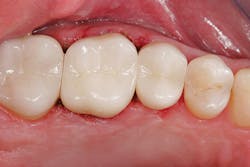

Figure 1: A patient presented for a new-patient examination. During the appointment, radiographic decay was noted on Nos. 12, 13, and 15. Treatment plan options were given to the patient. The patient elected to have Nos. 13 and 15 crowned and to have No. 12 restored with a new composite filling.

Figure 2: Intraoral images were shown to the patient, and it was explained that the existing crown on No. 14 (done several years ago) would not esthetically match the newly restored teeth. Also, the anatomical contours of the new porcelain restorations would be less ideal, due to the anatomy of the existing crown. Doing all three porcelain restorations at the same time would allow the contacts to be made more ideal and the crowns made to look similar. The patient elected to have all of the restorations in the quadrant completed during the same visit.

Figure 3: When the patient returned, e.max crowns were bonded with Variolink Esthetic Dual Cure (Ivoclar Vivadent), and the Picasso Lite laser (AMD Lasers) was used to achieve ideal isolation. The buildups and fillings were done with the same materials, Tetric EvoCeram Bulk Fill and Tetric EvoFlow Bulk Fill, allowing for more efficient quadrant dentistry. The same adhesive, Adhese Universal, was used for the fillings, buildups, and bonding of the restorations.

Figure 4: Immediately after bonding, the postoperative results were ideal contact areas and improved esthetics.